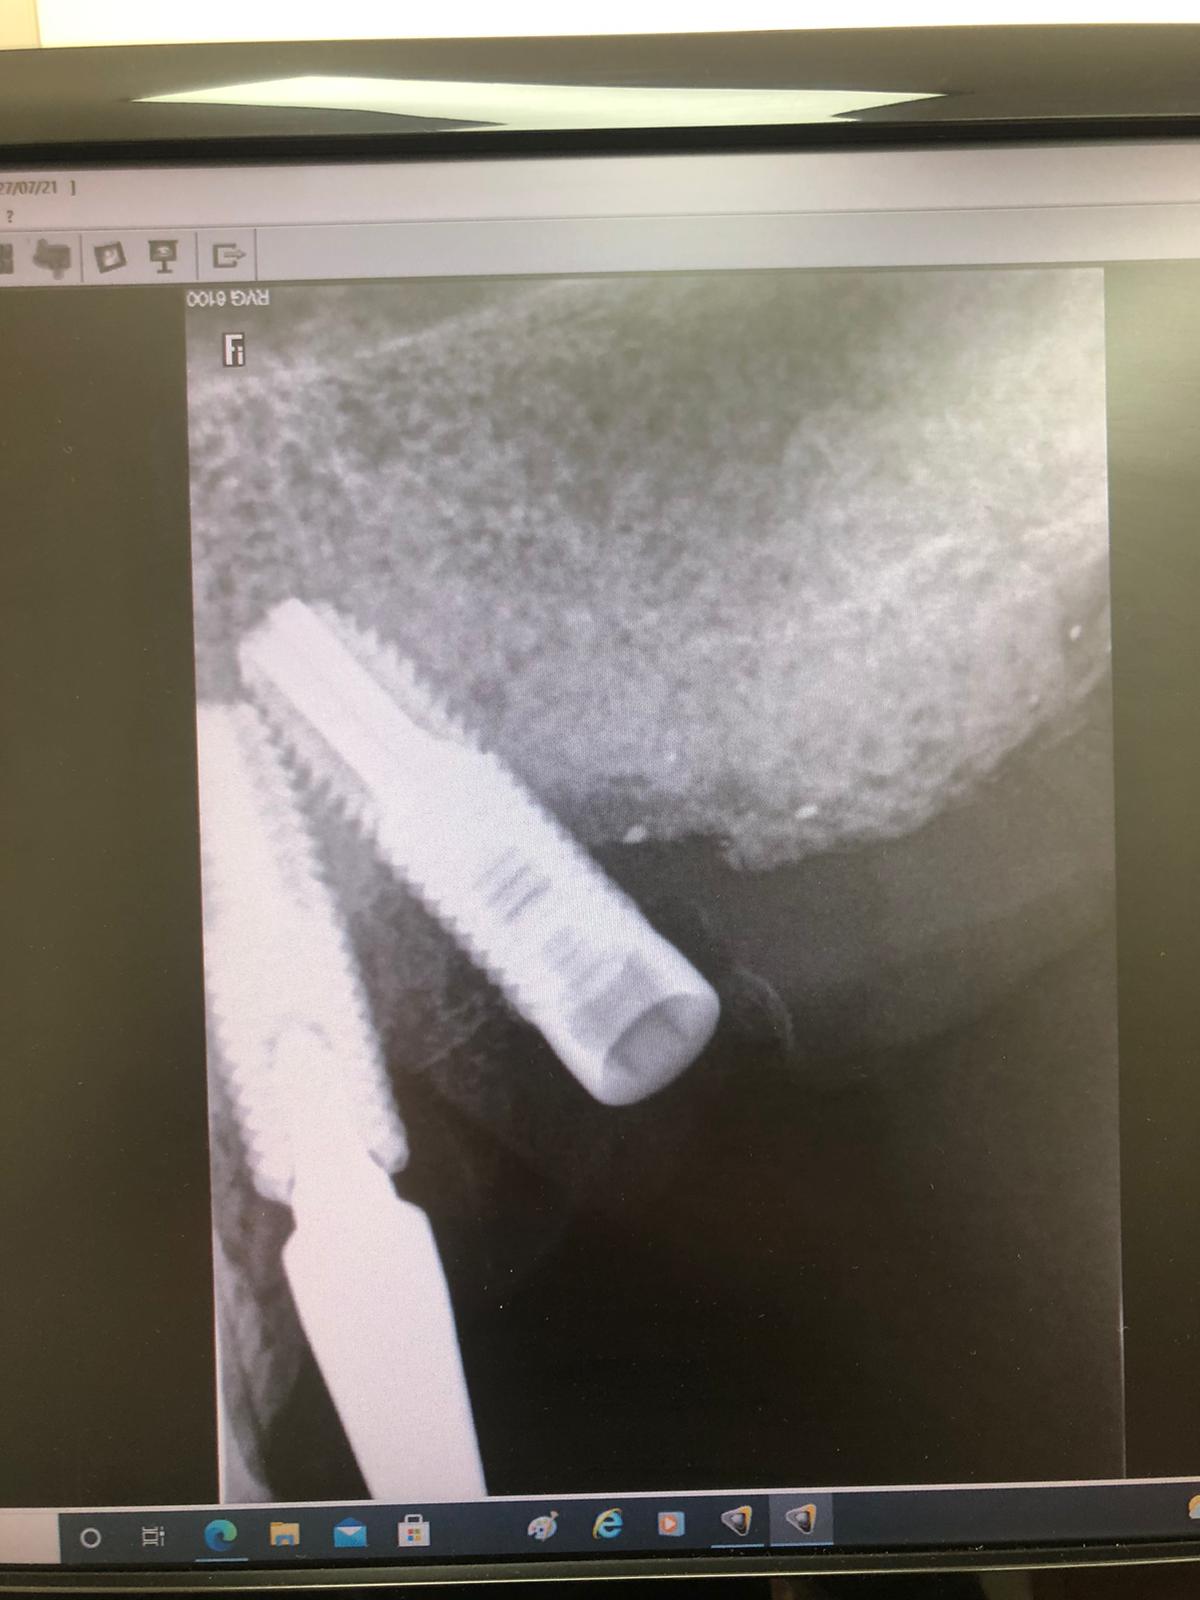

El paciente es un gran bruxómano y rompió hace tres años el implante Mesial (flecha en la imagen), pero no rompió solo la rosca del aditamento, sino también la cabeza del implante entera, quedando solo un resto de hueco roscado (comparar la anatomía de los implantes) en el que lo único que se pudo hacer, debido a que el implante tenía la conexión rota, fue roscar el aditamento ASATIM, pero solo la zona roscada y no el refuerzo y cono del implante, el cual había desaparecido (flecha en la imagen).

En nuestra clínica pusimos un aditamento de tornillo pasante en el implante distal. Y con esto se rehízo la prótesis. Así ha estado hasta este momento en el que aparece con la rosca de este tornillo pasante distal roto y dentro del implante (círculo en la imagen).